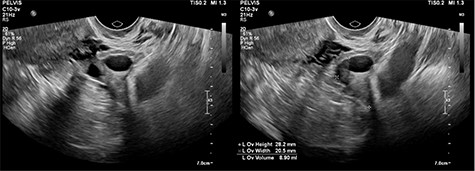

CT abdomen showed two cystic structures in the pelvis, and follow-up ultrasound demonstrated a 5.8-cm unilocular simple cyst contained within the right ovary, and a 3-cm left tubo-ovarian complex with associated hydrosalpinx (Figs 1–3).

Ultrasound imaging of the right ovary, demonstrating a simple cyst.